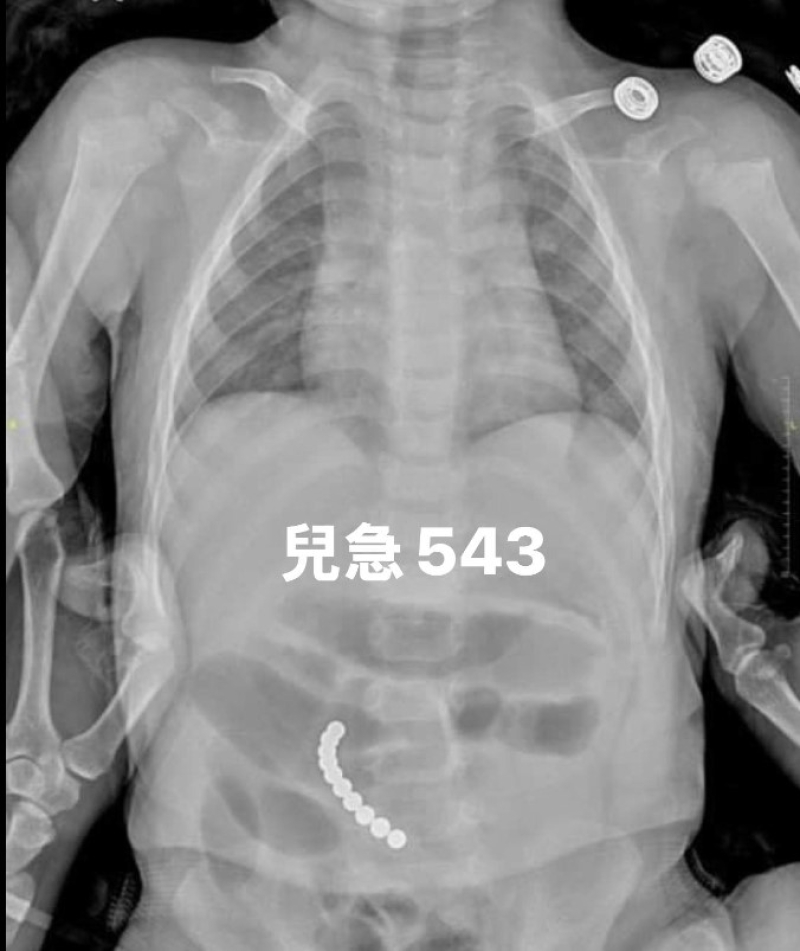

โดย แพทย์จึงรีบจัดตรวจเอ็กซ์เรย์ช่องท้องทันที และพบว่า บัคกี้บอล หรือ ลูกปัดแม่เหล็ก โดยบัคกี้บอลทั้ง 10 เม็ดได้ติดกันเป็นพวง จนทะลุลำไส้และเกิดภาวะเยื่อบุช่องท้องอักเสบ

หลังจากที่ทีมแพทย์ช่วยกันควบคุมสัญญาณชีพของเด็กให้คงที่แล้ว ได้ทำการตรวจเอกซเรย์ช่องท้อง และพบว่า เป็นบัคกี้บอลอีกแล้ว จำนวนถึง 10 เม็ด

การกลืนบัคกี้บอลทำให้ลำไส้ของเด็กทะลุและเกิดภาวะเยื่อบุช่องท้องอักเสบ ดร.อู๋ชางเถิง ตกใจมาก และจึงรีบติดต่อศัลยแพทย์เด็กให้พาเด็กชายเข้าห้องผ่าตัดด่วนเพื่อเอาบัคกี้บอลทั้ง 10 เม็ดออก เมื่อแม่เห็นบัคกี้บอลที่เอาออกมา ก็ยังคงตกใจไม่หายและบอกว่า "ต่อไปนี้จะไม่กล้าให้ลูกเล่นของแบบนี้อีกแล้ว